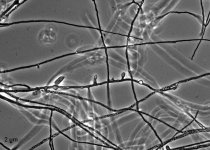

| Species Name: | Blastomyces helicus |

| Synonyms: | Emmonsia helica |

| Taxonomy: | FUNGI Ascomycota, Eurotiomycetes, Onygenales, Ajellomycetaceae |

| Substrate: | pleural fluid from liver transplant patient who died of fungemia, septic shock and pneumonia; isolated twice from blood and pleural effusion |

| Characters: | HUMAN/ ANIMAL PATHOGEN fungal pneumonia in immunosuppressed patient - (Click for publications citing UAMH 11294) |